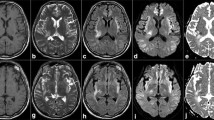

In decreasing order, involvement of typical locations was as follows: medial thalamic nuclei, n = 24/47 (51%); PAG, n = 22/47 (47%); MB, n = 16/47 (34%); tectal plate, n = 13/47 (28%); and hypothalamus, n = 7/47 (15%) (see Table 1). In all these areas with positive diagnoses, the hyperintensities detected on FLAIR images (n = 36/47, 77%) were stronger associated with MRI positive cases (χ2 = 47.0; P < 0.001) than those on T2WI (n = 17/47; 36%; χ2 = 8.1; P = 0.004), indicating that FLAIR images were crucial for diagnosing WE. Concomitant contrast enhancement (n = 18/47, 38%), diffusion restriction (n = 12/47, 26%), or presence of hemosiderin (n = 7/47, 15%) were also observed. Figures 2, 3, 4 and 5 depict four instructive cases with predominantly typical neuroimaging findings. Of the seven patients with signal loss on hemosiderin-sensitive sequences, four demonstrated microbleeds in the MB on SWI, as opposed to simultaneously acquired T2*WI (see Fig. 5). Isolated anatomical involvement was present only in PAG (n = 4/36, 11%) or MB (n = 1/36; 3%), but was less frequently observed (χ2 = 47.0; P < 0.001) than combined lesions (n = 31/36; 86%).

Characteristic brainstem and thalamic involvement in a 56-year-old female alcoholic with Wernicke encephalopathy. Hyperintense signal changes of the pontine tegmentum (a, b; arrow), the superior cerebellar peduncle (b, arrow), the quadrigeminal plate and the periaqueductal grey matter (c, d; arrow), paramedian thalamic nuclei (e, arrow), hypothalamus (e) and pulvinar of the thalamus (f, arrow); a–f axial fluid-attenuated inversion recovery

Hyperintense signal changes of the periaqueductal grey (a, b; arrow) and the inferior colliculus (a, b; white arrowhead) with distinct enhancement on contrast-enhanced (CE) T1-weighted images (WI) (c–e; white arrowhead) in a 66-year-old male alcoholic. Hyperintense lesion in the hypothalamus (b, black arrowhead; axial fluid-attenuated inversion recovery) and contrast enhancement of the mammillary bodies (c, black arrowhead; axial CE-T1WI)

Swelling with hyperintense signal changes of the mammillary bodies on T2-weighted images (WI) and fluid-attenuated inversion recovery images (a, b axial; d, e coronal; arrow) with slight enhancement on axial contrast-enhanced T1WI (c, arrow) in a 63-year-old female non-alcoholic. Note additional hyperintense signal changes of the hypothalamus (a, b, d, e)

Symmetrical signal loss in the mammillary bodies (MB) due to microhemorrhages (b, arrow; axial susceptibilit- weighted imaging (SWI)) with phase shifting, indicating paramagnetic effects of iron (c, arrow; SWI-phase map), not visible on T2*WI (a, arrow). Axial T2WI (d, arrow) and fluid-attenuated inversion recovery images (e, arrow) showing inhomogeneous hyperintense signal changes of the MB with slight enhancement on axial contrast-enhanced T1WI (f, arrow) in this 53-year-old male alcoholic

Distinct hemorrhages in the paramedian thalamic nuclei (e, arrow), the periaqueductal grey and the quadrigeminal plate (f, arrow), the mammillary bodies (f, arrowhead) and the pontine tegmentum (g, h, arrow) with inhomogeneous signal loss on susceptibility-weighted imaging (SWI) in a 61-year-old male alcoholic. a–d corresponding hyperintense lesions on axial fluid-attenuated inversion recovery images (arrow); k sag. T2WI (arrow). Enhancement of the inferior colliculus on contrast-enhanced T1WI (j, l, arrowhead) and partially hyperintense lesions on T1WI (i, l, arrow). Note additional intraventricular clots

Hemorrhagic transformation of affected paramedian thalamic nuclei in a 49-year-old female alcoholic with Wernicke encephalopathy. Inhomogeneous signal changes on axial T2-weighted images (WI) (a, arrow), punctuate signal loss on axial susceptibility-WI (b, arrow) and patchy enhancement on contrast-enhanced T1WI (c before, d after administration of contrast agent; arrow). Note additional enhancement of the hypothalamus and the quadrigeminal plate (e, arrows)

a–d Extensive involvement of the optical pathway, internal capsule, brainstem and cerebellar peduncles in a 43-year-old male alcoholic suffering from acute Wernicke encephalopathy with hyperintense lesions on axial fluid-attenuated inversion recovery images. e–h Follow-up MRI 78 days later disclosed impressive lesion regression after intravenous vitamin B1 substitution, and neurological examination was unremarkable